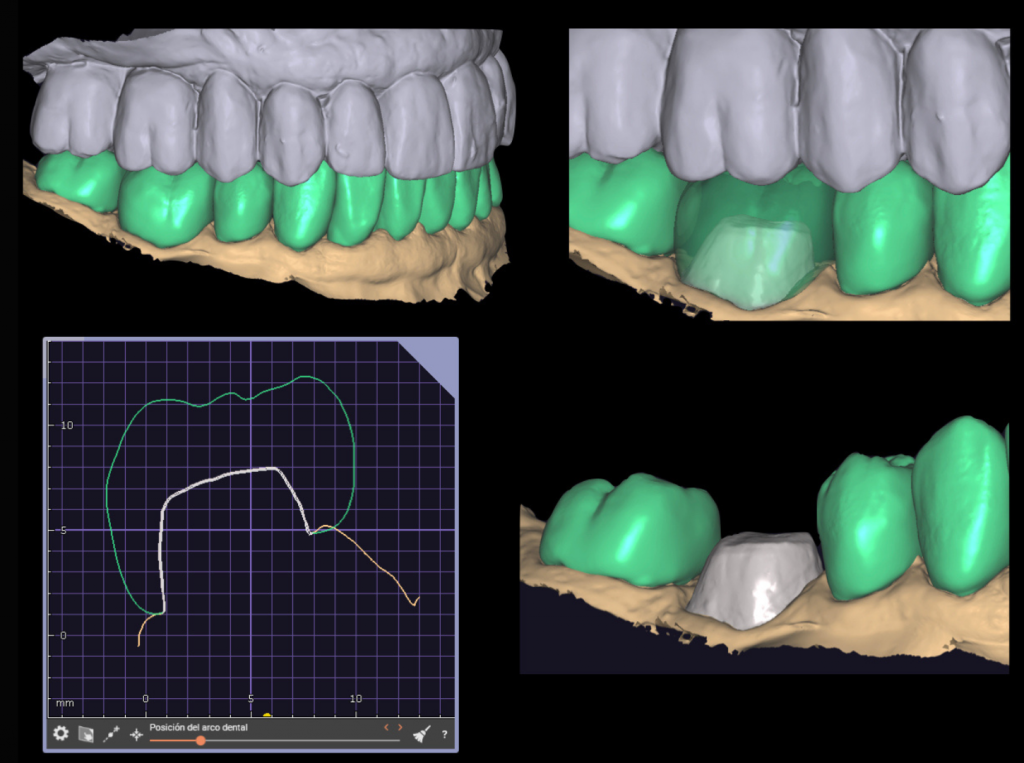

Es importante destacar que para obtener estos resultados es esencial utilizar magnificación en el tratamiento y llevar a cabo un aislamiento adecuado. Un especialista en endodoncia está capacitado para utilizar herramientas de alta tecnología para garantizar una mayor precisión y un mejor resultado en el tratamiento.

En nuestra clínica dental, contamos con especialistas altamente capacitados y con la última tecnología en endodoncia para garantizar un tratamiento de alta calidad y resultados impresionantes. Sabemos lo importante que es para ti conservar tus dientes naturales y estamos comprometidos a hacer todo lo posible para asegurarnos de que tengas una sonrisa sana y radiante.